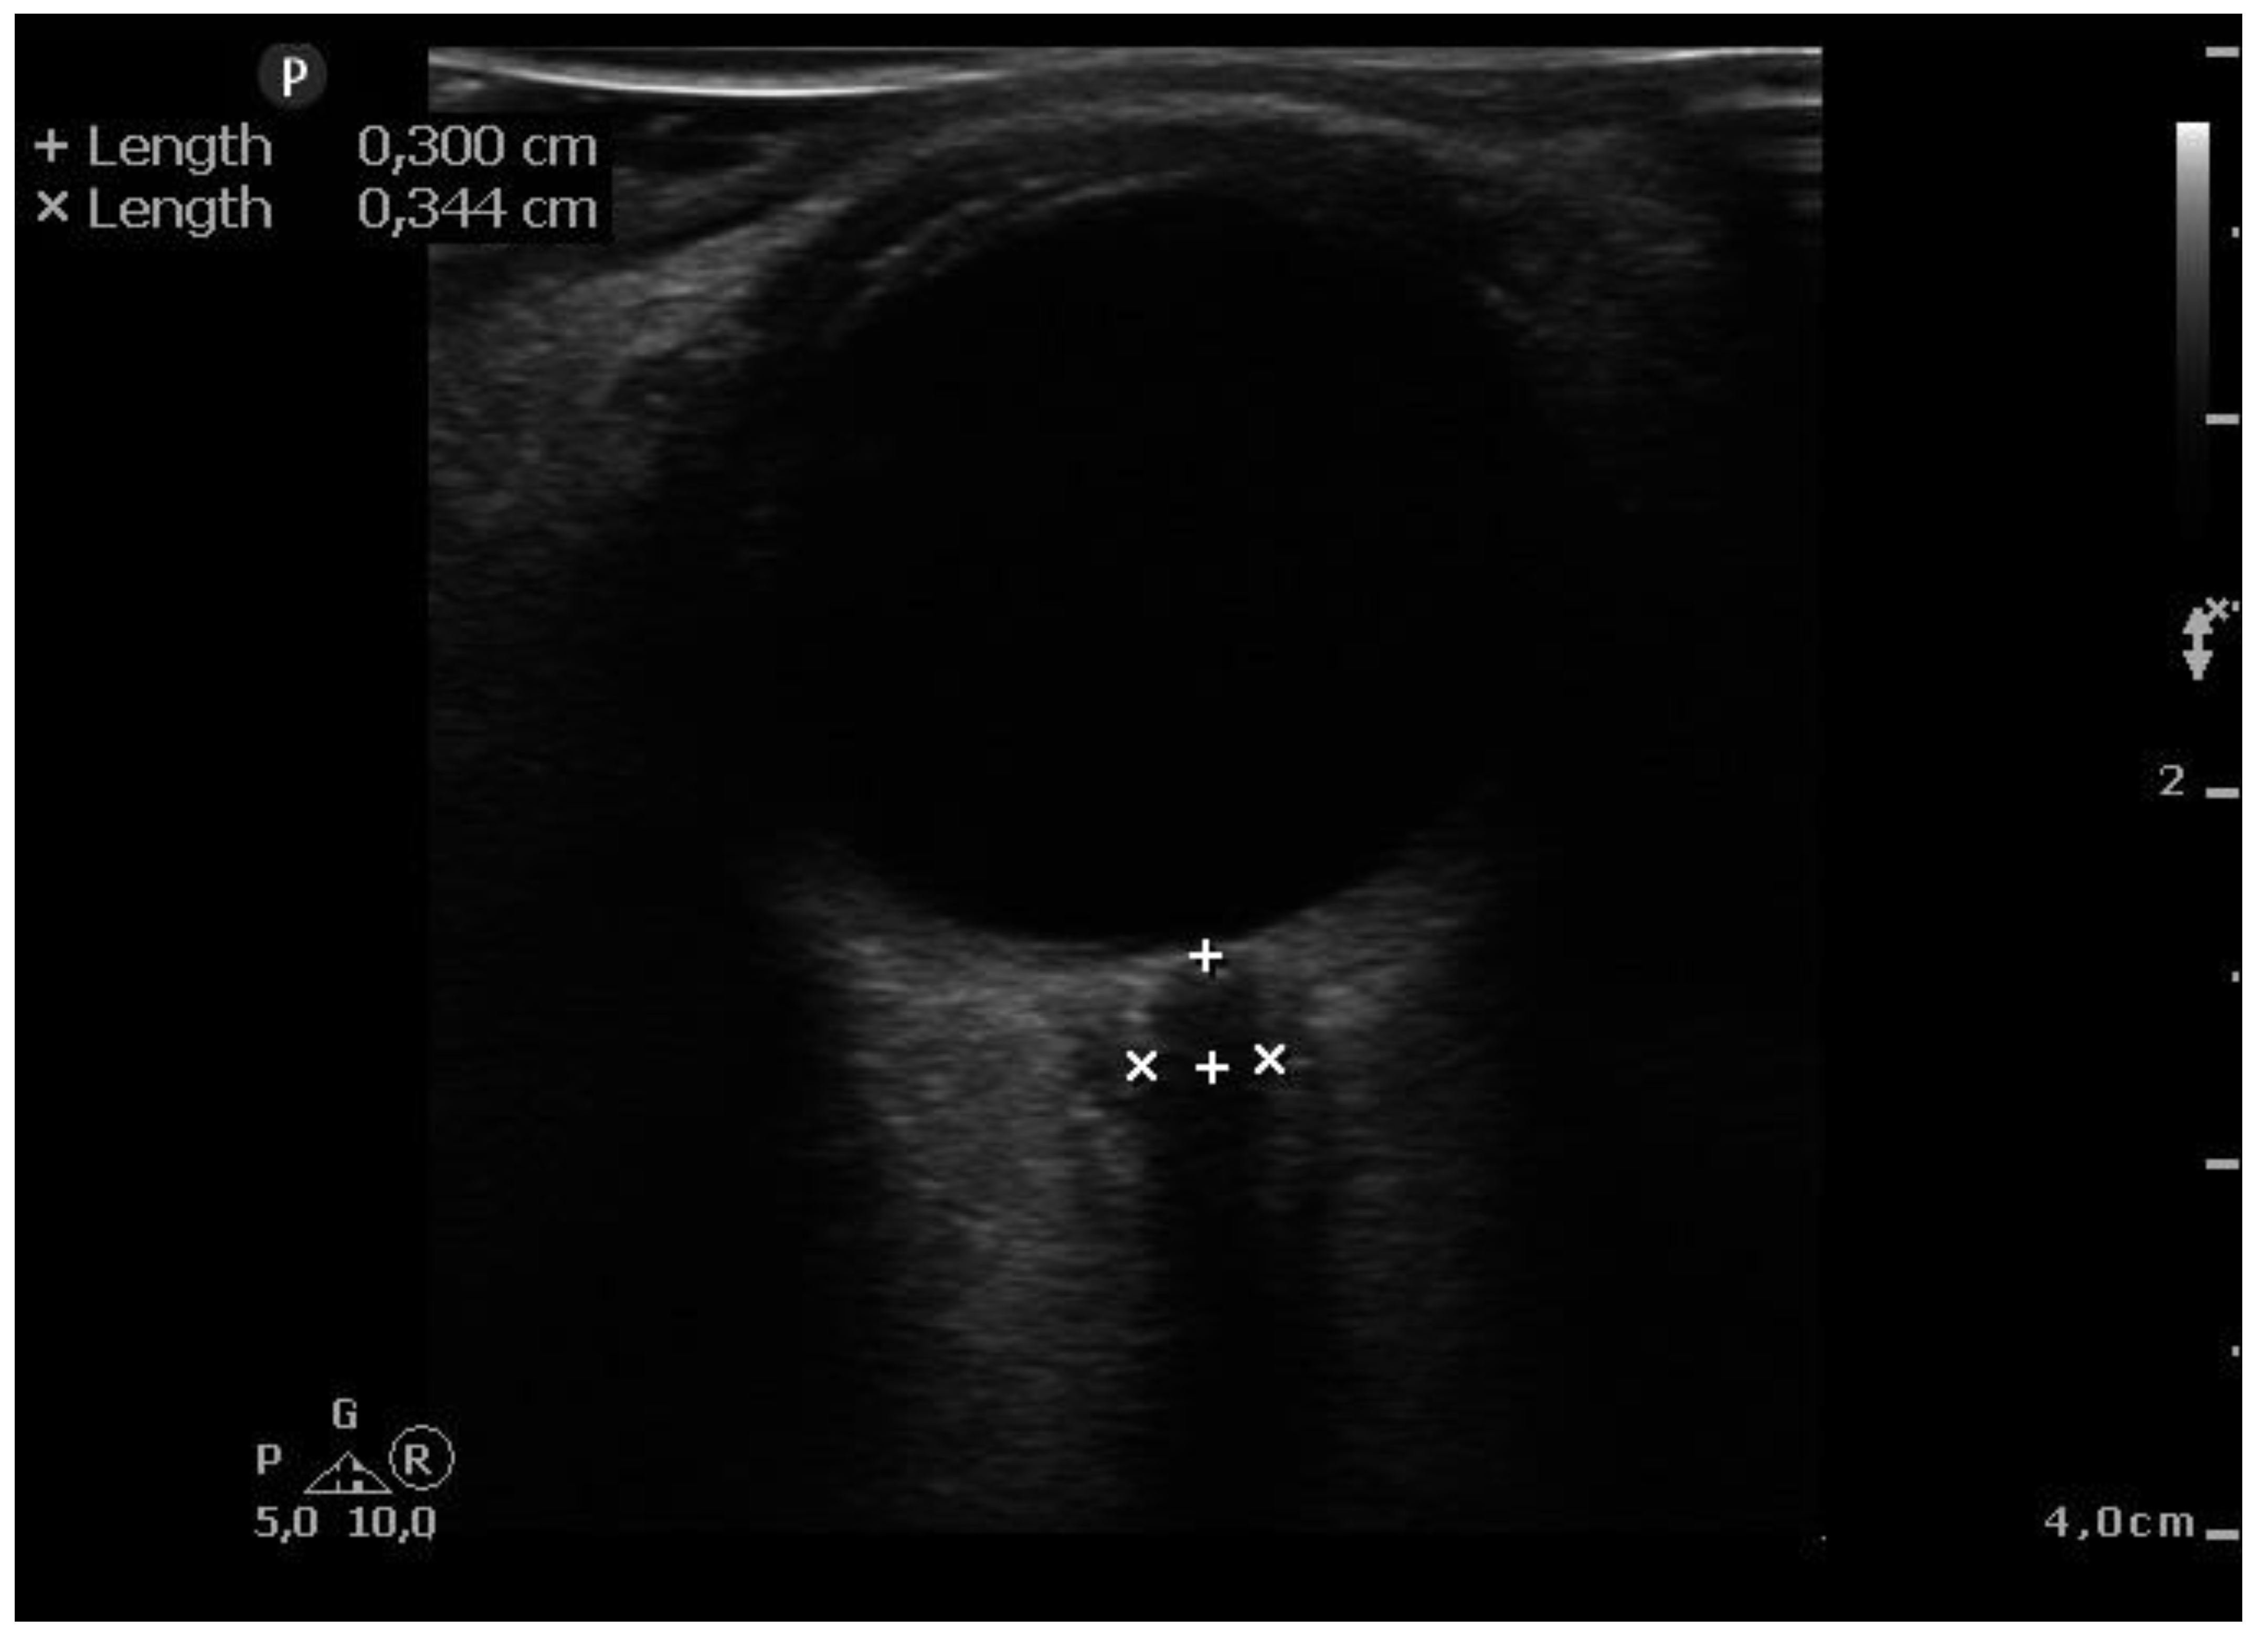

When general anesthesia induced and hemodynamically stable conditions were reached, ultra-sonographic measurements were taken. It was before introducing pneumoperitoneum (10-15 mmHg of insufflation pressure) and in the steep Trendelenburg position (45° incline) After applying water soluble lubricant, the probe was placed on the closed upper eyelid with minimal pressure in a direction parallel to the eyelid. Second measurements were taken after surgery end and immediately after position change to a supine position. ONSD ultrasound was performed using a 7.5 MHz line head L12-4 (PHILIPS SPARCK 22100 Bothell Everett Highway Bothell, WA, 98021 USA). (Figure 1.) Two sonographers (T.S. and E. K.), who had performed > 50 scans measured ONSD, took three measurements of the same patient before and after the procedure, and the average of these measurements was taken as the final result. The ONSD measurement was standardized by measuring at a depth of 3 mm outside the posterior wall of the eyeball. Because other investigators [16,18] showed that ONSD > 5.0 mm correlated with increased intracranial pressure, and the cut-off point of 6.0 mm increases the sensitivity and specificity of the test, we used 6.0 mm as the reference value.

Figure 1. Ultrasonography image of optic nerve sheath. Optic nerve sheath diameter is measured 3 mm behind the optic disc.